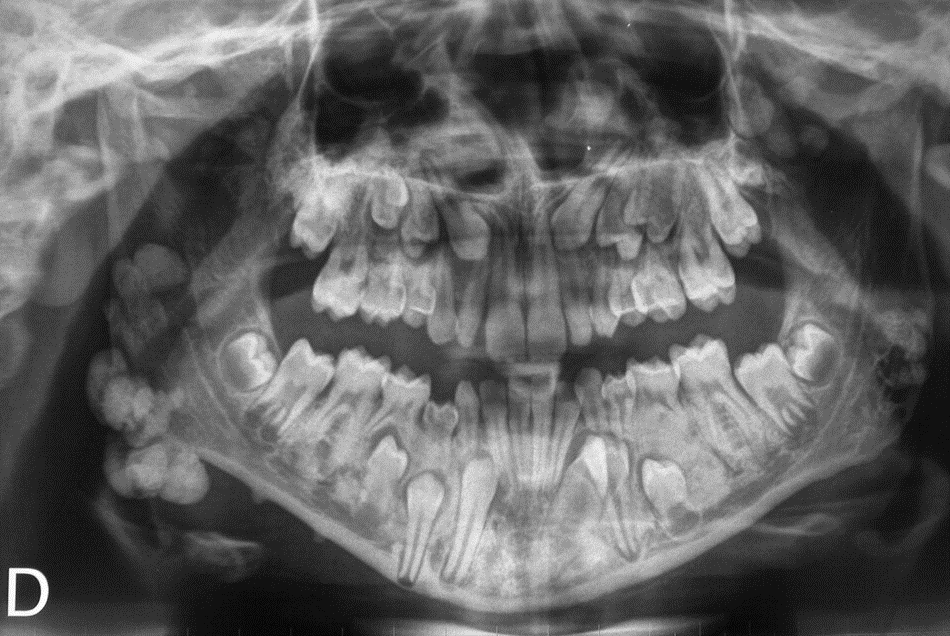

4 / 25

4. (Select ONE OR MORE correct answers)

The radiograph shows evidence of